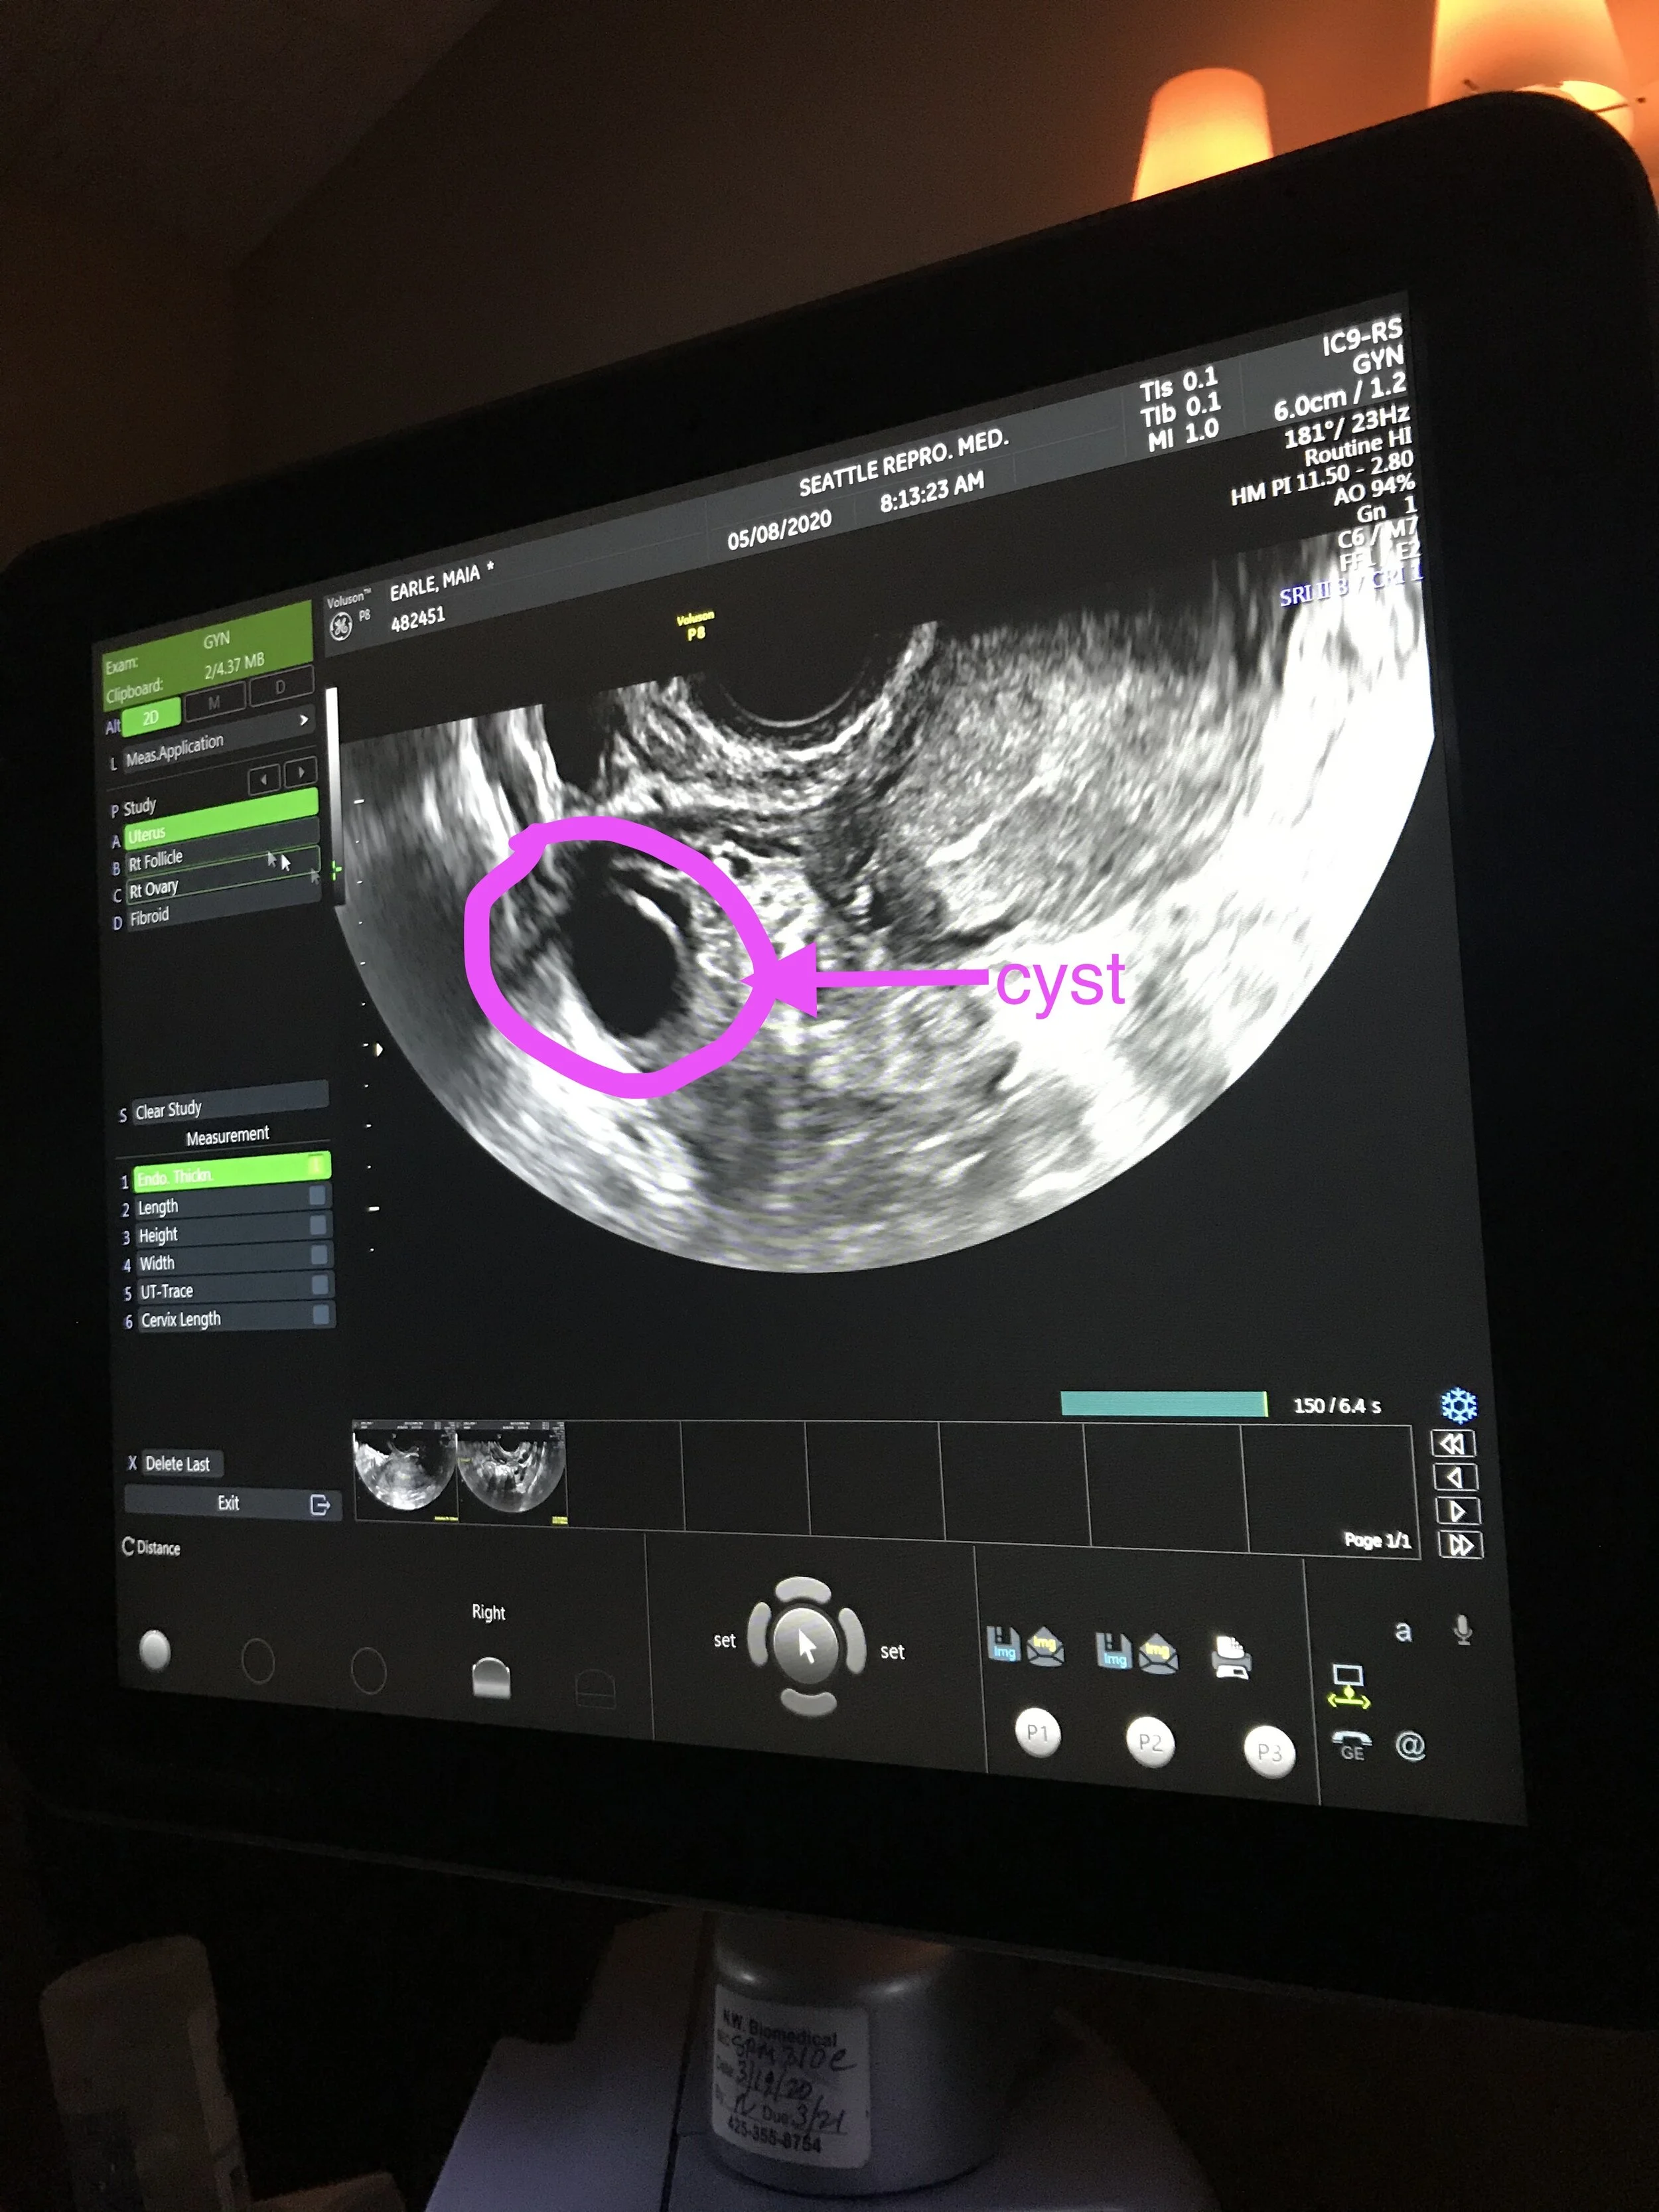

one of two cysts found in the right ovary

Today I had my Suppression Check ultrasound appointment. After taking birth control for ten days in order to allow Seattle Reproductive Medicine to “take the reigns” of my cycle, today was the day we used ultrasound to check for follicles, cysts, and observe the uterine lining. Unfortunately, two cysts were observed in the right ovary.